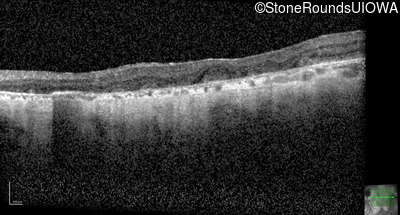

Optical Coherence Tomography - Left - 20/200

Exemplar / OCT Stack